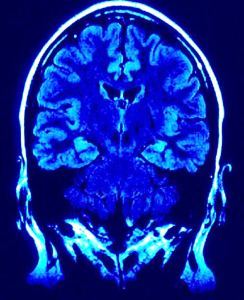

TSC is a genetic disease that is characterized by malformations and an overgrowth of cells in the brain and other organs. Everolimus is an mTOR inhibitor that blocks the mTOR pathway that is associated with the cell overgrowth. Other mTOR-associated disorders include cancers and neurological conditions, such as Alzheimer's disease, Type 2 diabetes and autism.